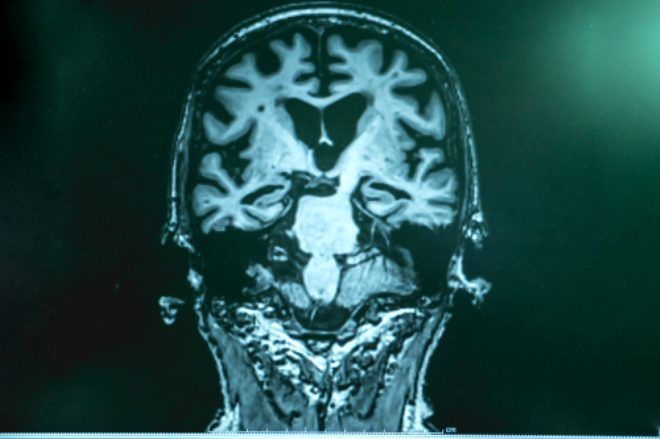

Nöroloji Uzmanı Doç. Dr. Hatice Balaban, Alzheimer hastalığının çeşitli belirtileri bulunduğunu belirterek, Bu rahatsızlığı yaşayanlar, randevularını, ocakta yemeği, evde anahtarı unutabilirler. Kelime bulma güçlüğü çekerler, sıkça 'şey´ derler. Ellerini eskisi gibi kullanamazlar. Giyinip soyunmada zorluk yaşarlar dedi.

Günümüzde her yaştan bireyin günlük yaşamında unutkanlığın ortaya çıkabilecek yaygın bir problem olduğuna dikkat çeken Balaban, şunları söyledi: Bu durumun çoğunlukla sebebi dikkat bozukluğudur ya da günlük koşuşturmalara bağlıdır ve bir hastalığa işaret etmez. Buna karşın unutkanlığın hastalığın bir parçası olan demans, kazanılmış zihinsel yetilerin sonradan bireyin günlük yaşam aktivitelerini etkileyecek derecede bozulduğu bir grup hastalığı kapsar.

Uzun süreli hafıza korunmuşken kısa süreli bellekte bozulmalar dikkati çeker. Zamanla, hastalığın ileri evrelerinde uzak bellek de bozulur. Bu bağlamda hasta, aynı soruları defalarca sorabilir. Anlattığı bir konuyu defalarca kez daha önce hiç anlatmamış gibi anlatabilir. Özel eşyalarını koyduğu yerleri kaybeder, randevularını, ocakta yemeği, evde anahtarı unutabilirler. Kısa süreli bellek problemleri yanında lisan bozuklukları görülebilir. Hastalarda en sık görülen ve dikkat çeken ise kelime bulma güçlüğüdür. Söyleyecekleri kelime yerine 'şey´ sözcüğünü sık kullanma görülür. Tutuk konuşma ve cümle uzunluğunun kısalması, evet-hayır şeklinde kısa kelimelerle yanıt verme diğer dikkat çeken durumlardır.

Beceri isteyen motor işlevlerin kaybı bir diğer durumdur ve ilerleyici beceriksizlik, sakarlık şeklinde anlatılır. Hastalar ellerini eskisi gibi kullanamadıkları, objeleri düşürdüklerinden yakınırlar. Üzerini giyip çıkarmada zorlanırlar ya da ters çıkarılmış bir elbiseyi düzeltemezler. Giyme işlemini başlatamaz ya da başarı ile tamamlayamazlar. Çatal, kaşık kullanmada zorlanırlar. Yazı yazma bozulabilir. Dikiş dikememe, marangozluk işlerinde beceriksizlik, mutfak ve diğer ev aletlerini kullanamama olabilir.

Bazı hastalarda ise daha ilginç olarak aradığı eşya gözünün önünde olduğu halde diğer nesnelerden ayırıp bulamama, okurken satırların birbirine karışması, yazı karakterlerinin bozulması görülebilir. Görme, işitme ve dokunma algılamasının bozulması da olabilir. Buna bağlı olarak yüzleri, sesleri ve objeleri tanıyamama, vücut tarafını belirleyememe ya da ayırt edememe ortaya çıkabilir. Henüz hastalığı durdurucu ya da tamamen tedavi edici bir ilaç geliştirilememiştir. Bununla birlikte unutkanlık şikâyeti olan bireylerde tanının erken konması ve tedavinin mümkün olduğunca erken başlanması oldukça önemlidir diye konuştu. (DHA)